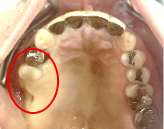

Before

After